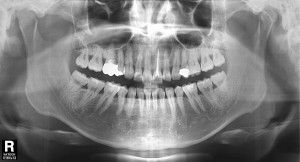

2013-06-19 초진pano#21,22

초진 내원시 찍은 환자분의 방사선사진입니다.  왼쪽 위 중절치와 측절치에 치근 아래에 동그란 모양의 잇몸뼈가 차있지 않는 것을 알 수 있습니다.